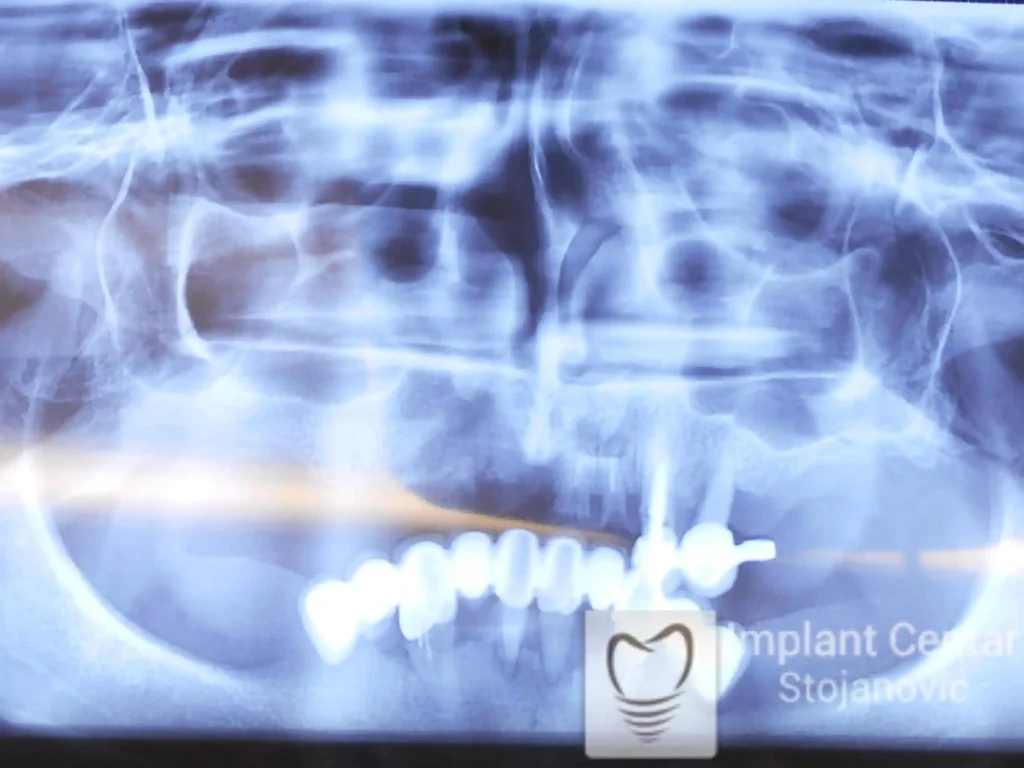

Na slici 1. i slici 2. prikazan je izgled pacijenta pre početka terapije – klinički i rendgenološki.

Nakon vađenja zuba, ugrađeni su implantati. Na slici 3 prikazan je ortopan snimak sa ugrđenim implantatima. Tokom perioda osteointegracije, pacijent je bio zbrinut fiksnim privremenim krunicama na implantatima, koje su izrađene samo dva dana nakon hirurške intervencije.